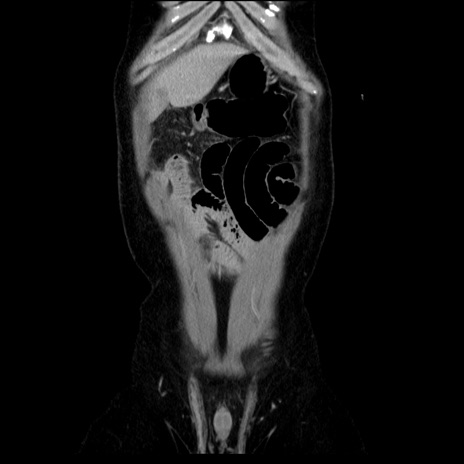

横断像